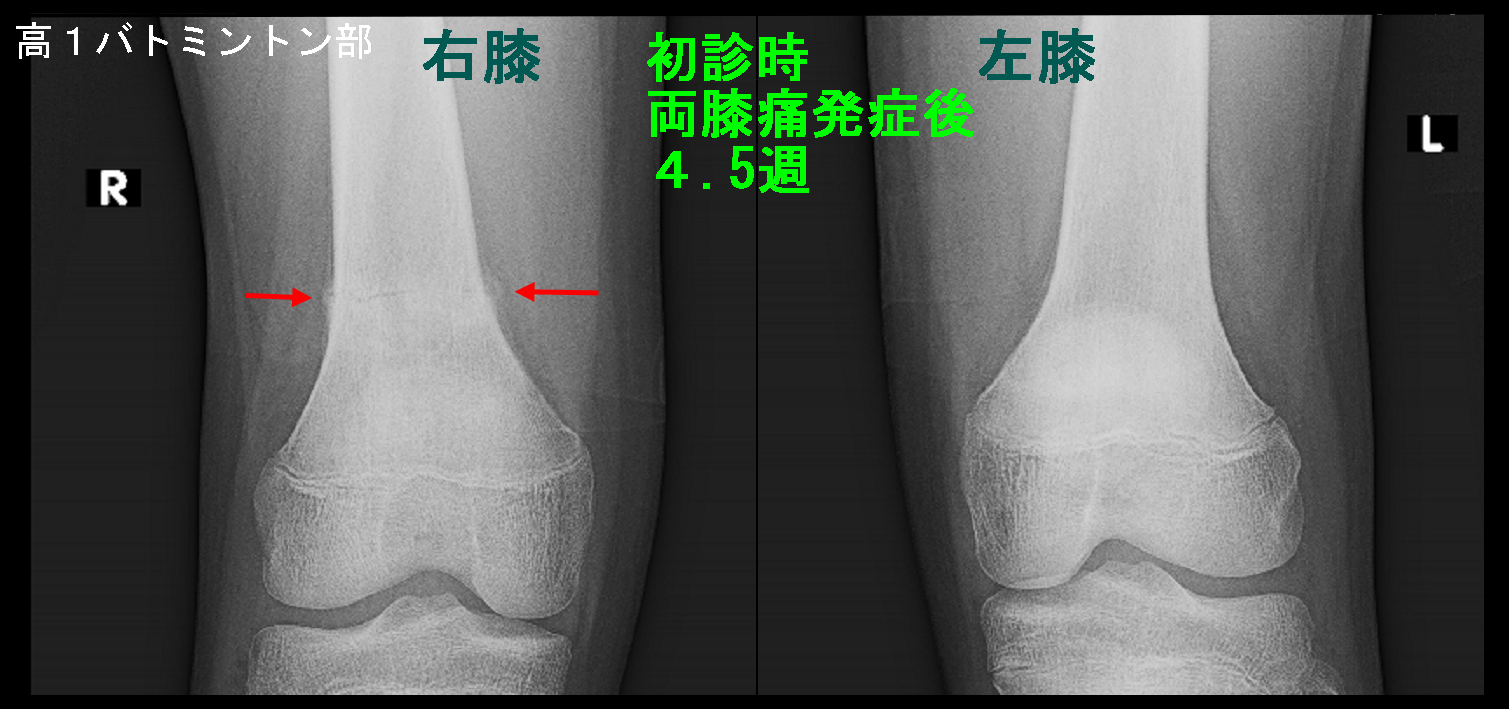

初診時のレントゲン像です。赤矢印で右大腿骨に仮骨(骨折を補強する新生骨)と薄い骨折線が確認できます。

初診時Xp.jpg